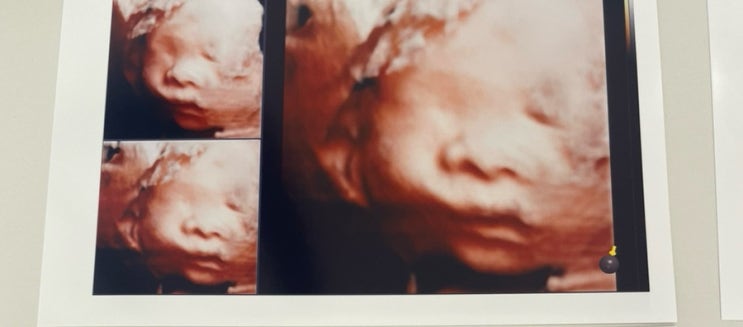

[임신]와이즈병원 임당검사+입체초음파 기록

26주 6일차에 다녀온 임당검사 입체초음파 임신하면서 26주 6일차에 몸무게가 무려 18키로나 증가한 산모.....